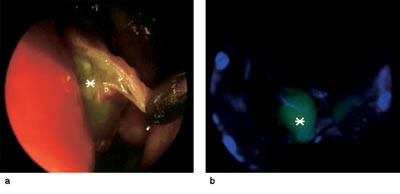

Pasient 1. En 61 år gammel kvinne ble operert på grunn av kronisk sinusitt. Etter operasjonen rant det klar væske fra nesen og lekkasjen økte når hun bøyde seg fremover. Væsken inneholdt 42 mg/l betasporprotein, en verdi som er forenlig med likvoré. CT-undersøkelsen viste en beindefekt i sentrale lamina cribrosa. Det kunne ikke avgjøres om det forelå en ensidig eller en bilateral lekkasje. Hun ble operert endoskopisk med natriumfluoresceinfargeteknikk. Under operasjonen fant man lekkasje på begge sider av lamina cribrosa, og defektene ble dekket med frie transplantater av fascia lata (fig 1).

Fargeteknikken med bruk av natriumfluorescein ble først beskrevet i 1960 og senere utviklet videre (18, 19). Natriumfluorescein er et fargestoff som er tillatt til intravenøs eller oral bruk, men det er ikke beregnet som diagnostisk hjelpemiddel for intratekal injeksjon. Fargestoffet fordeler seg i intraduralrommet i løpet av noen timer etter lumbal injeksjon og blir utskilt renalt i løpet av tre dager. En fordel med natriumfluorescein er at det både kan brukes til å påvise om det foreligger en cerebrospinalvæskelekkasje og til å finne lekkasjestedet ved endoskopisk eller mikrokirurgisk kirurgi. Som bivirkninger ses forbigående svakhet i underekstremitetene, nummenhet, grand mal-anfall, opistotonus og hjernenervepareser (20). I et materiale på 925 pasienter fant man grand mal-anfall hos tre pasienter. Alle tre fikk natriumfluorescein injisert suboksipitalt (21). Alvorlige og varige bivirkninger er ikke beskrevet i litteraturen ved lumbal injeksjon og riktig dosering. Pasientene bør informeres om kjente bivirkninger og om mulige behandlingsalternativer. Ved bruk av natriumfluorescein legges en lumbaldrenasje dagen før inngrepet. 0,5 ml av en 10 % steril natriumfluoresceinløsning fortynnet med 10 ml autolog cerebrospinalvæske injiseres langsomt i spinalkanalen. Endoskopisk sporing av natriumfluorescein skjer ved hjelp av et blåfilter på lyskilden og et gulokular på endoskopet. Begge forsterker synligheten av fluorescensen (fig 4). Lumbaldrenet blir liggende i tre dager for å redusere det intrakraniale trykket den første tiden etter lukkingen av lekkasjen og dermed redusere faren for ny lekkasje.